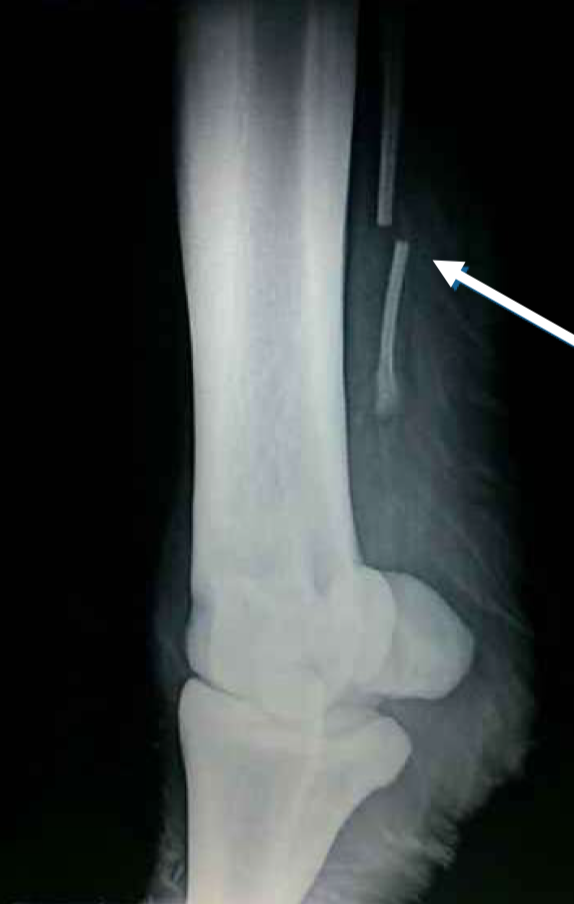

Diagnosis?

Fractured splint bone

Fracture of the middle aspect of the splint bone:

All of the above

T/F: Splint bone fractures are caused by hyperextension of the fetlock or external trauma

True